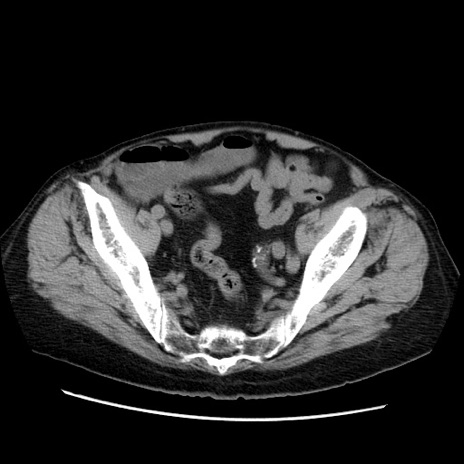

【症例】70歳代男性

【現病歴】肝硬変・肝細胞癌にてかかりつけの方。約9時間前に食後より腹痛出現。症状が徐々に増悪し、嘔吐出現したため来院。

【既往歴】肝硬変、肝細胞癌(RFA、TACE後)

【身体所見】意識清明、表情苦悶様、BT 36℃、BP 129/78mmHg、P 88bpm、SpO2 97%(RA)、右上腹部から心窩部にかけて圧痛あり、反跳痛なし、筋性防御あり。